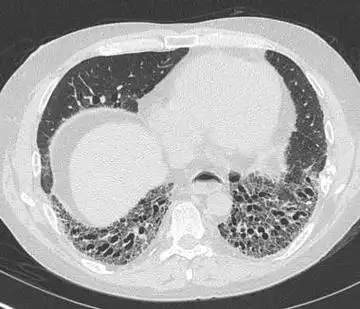

【病例讨论】蜂窝肺改变-迁延3个月,抗生素应用仍不见好转